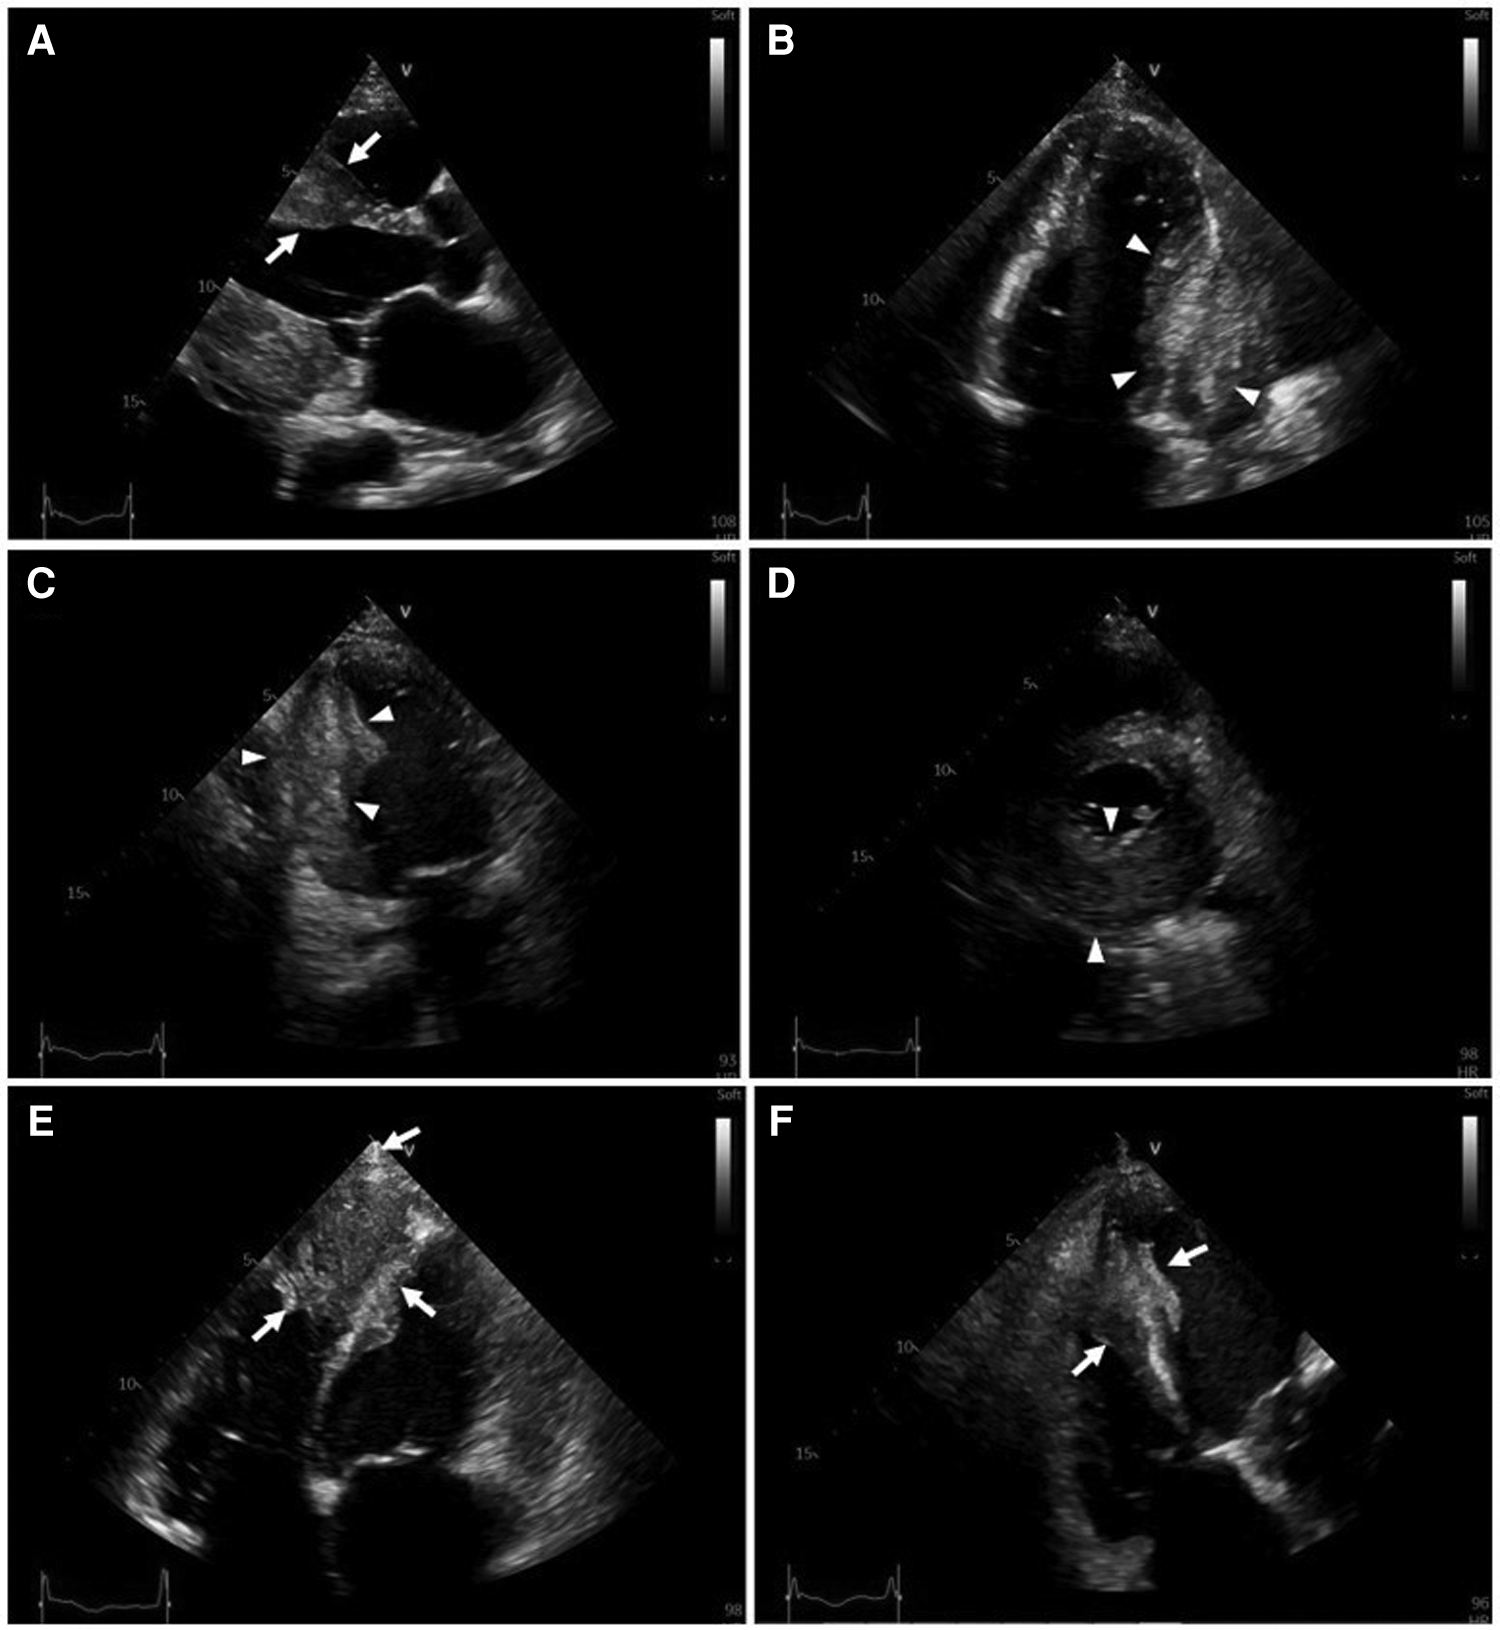

Figure 2

Transthoracic two-dimensional echocardiography (2D-TTE). 2D-TTE reveals two large heterogeneous masses characterized by ill-defined borders: one involving the lateral, inferior and posterior portions of the left ventricular wall (white arrowheads), and another involving the apex and ventricular septum (white arrows). (A) Parasternal long-axis view. (B) Four-chamber view. (C) Two-chamber view. (D) Parasternal short-axis view at the papillary muscle level. (E) Modified four-chamber view. (F) RV-focused apical four-chamber view.

Serial hs-cTnT measurements and ECGs were obtained. A comprehensive transthoracic echocardiogram (TTE) was performed on the following day. On serial ECGs, STE persisted and there was no development of pathological Q waves (Figures 1B, C). Laboratory studies showed that hs-cTnT stabilized at a high level: on admission 0 h 173.1 ng/L, 1 h 167.3 ng/L, 3 h 159 ng/L, on discharge 180 ng/L (<14 ng/L); elevated N-terminal pro-B-type brain natriuretic peptide (NT-pro-BNP) was 1391 pmol/L < 14.47 pmol/L). TTE unveiled two large heterogeneous masses, which were characterized by ill-defined borders: one involved the lateral, inferior and posterior portion of the left ventricular wall, and another involved the apex and ventricular septum portion (Figure 2). The involved ventricular walls were significantly thickened and akinetic, which did not correspond to coronary perfusion territories. Left ventricular systolic dysfunction (biplane left ventricular ejection fraction of 35%), and right ventricular systolic dysfunction (tricuspid annular plane systolic excursion of 15 mm and fractional area change of 30%) were detected.